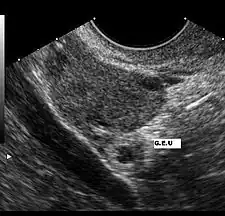

Diagnóstico por la imagen

El ultrasonido es probablemente la herramienta más importante en el diagnóstico de un embarazo extrauterino, especialmente si se combina con otros métodos. Con mayor frecuencia, se utiliza para confirmar un embarazo intrauterino.[12] La visualización de un saco intrauterino, con o sin actividad cardíaca fetal, a menudo es suficiente para excluir un embarazo ectópico.[11] La excepción es en el caso de un embarazo heterotópico, la combinación de embarazos intra y extrauterino que, aunque es una situación excepcional, se ven cada vez más frecuentes, entre 1 de 4000 a 1 de cada 30 000 embarazos espontáneos. El estudio de los anexos uterinos por un ultrasonido es obligatorio en pacientes sometidas a estimulación ovárica y la reproducción asistida a pesar de la visualización de un embarazo intrauterino, porque son pacientes que tienen 10 veces mayor riesgo de embarazo heterotópico.

El ultrasonido transvaginal tiene mayor resolución que el abdominal y puede ser usado para visualizar un embarazo intrauterino 24 días después de la ovulación o 38 días después del último período menstrual, que suele ser alrededor de 1 semana antes de los que es posible visualizar un ultrasonido transabdominal. El saco gestacional —un término ecográfico y no anatómico— es la primera estructura que se reconoce en un ultrasonido transvaginal.[11] Se ve en el ultrasonido como una zona ecogénica gruesa en torno a un centro hipogénico correspondiente a la reacción decidual trofoblástica que rodea el saco coriónico. Las estructuras que representan a un embrión en desarrollo aún no se pueden reconocer sino hasta una mayor edad gestacional.[13]